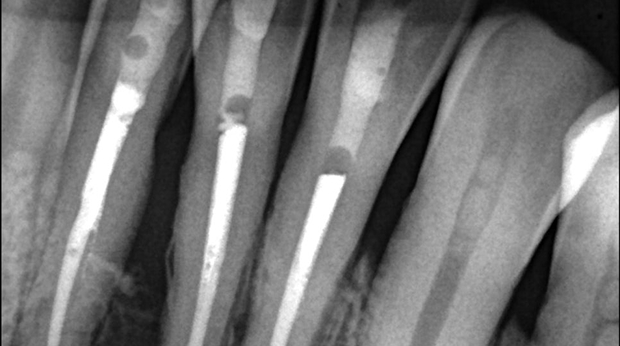

매복 사랑니 발치

임플란트와 사랑니 발치는 외과적 시술로 잇몸을 절개하는 외과적 시술은

짧으면 짧을 수록 시술 후 붓기와 통증이 최소화됩니다.

치과의사 경력 14년차 구강외과 전문의가 빠르고 안전하게, 아프지 않게 수술해 드립니다.